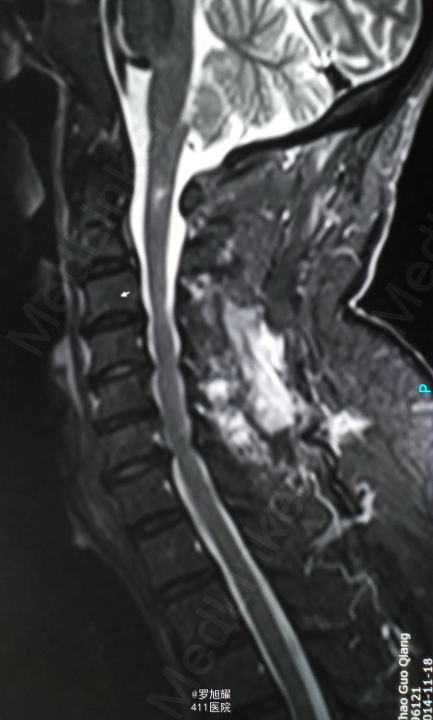

入院立即给与大剂量甲强龙冲击治疗,辅以甘露醇脱水消肿,兰索拉唑保护胃黏膜,腺苷钴胺恩经复营养神经,伤后10天复查MRI脊髓信号增高明显,两周后生命体征稳定,肢体感觉和肌力见部分恢复,行颈2椎弓根螺钉、颈3侧块钉内固定术,因神经压迫不明显未行椎板切除减压。 术后3月骨折线基本消失,患者感觉肌力几乎完全正常,右肩残留疼痛磁共振检查发现肩袖损伤,暂予局封治疗症状缓解。

该患者术后4月随访瘫痪症状完全消失,感觉正常,右侧肌力已经接近5级,但Mri随访T2加权像仍可见明显的脊髓高信号,但是影像学上脊髓变性和患者的症状没有明显的相关性,说明神经功能的代偿潜能还是非常巨大的,各位老师和同仁是否同意呢?